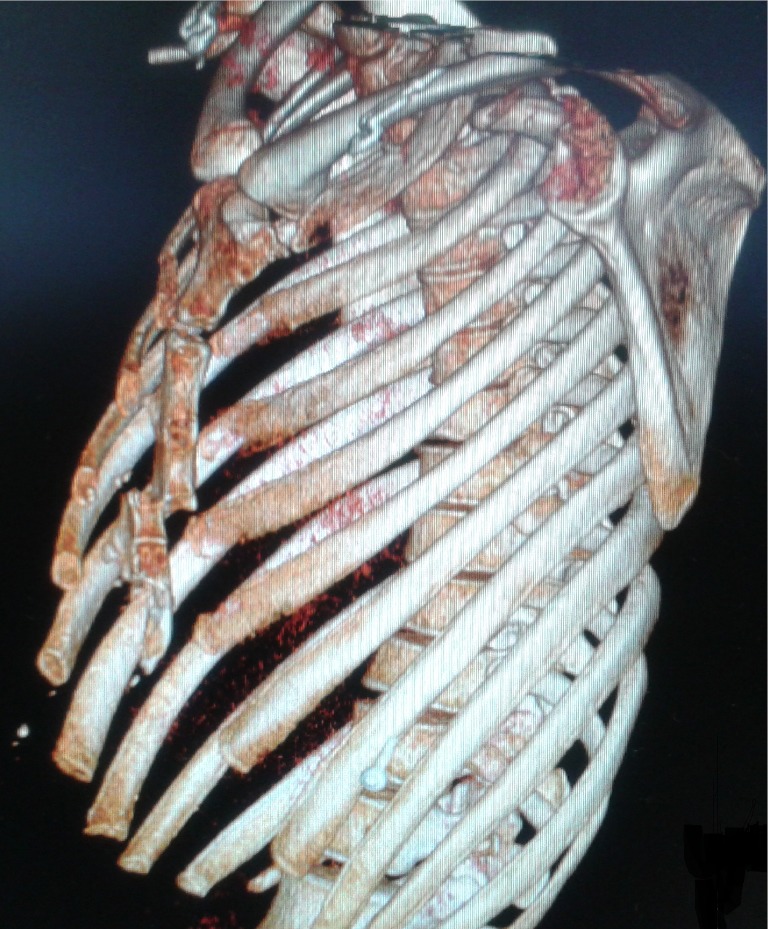

Figure 2.

3-D CT scan shows a displaced fracture of corpus sternum where the upper fragment slipped behind the lower part without any ribs or vertebral column injuries